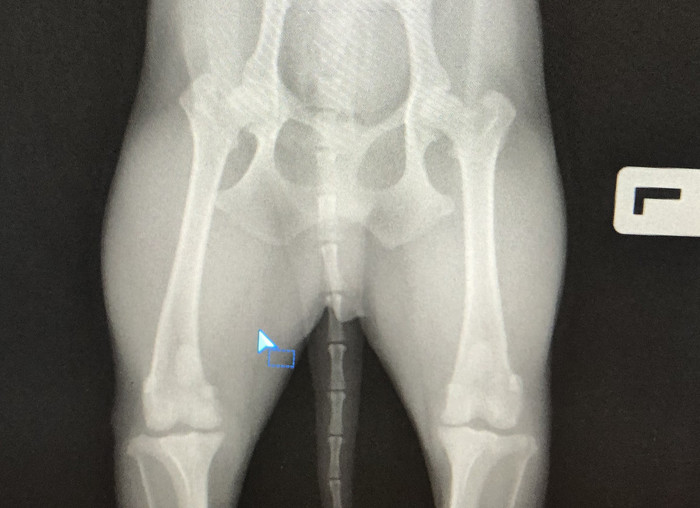

Собакен 11 лет, 5 кг, смесь чиха и тоя. Глава семьи.

На прошлой неделе перестал наступать на заднюю левую лапу.

На сл день перестал хромать, отвезли его в клинику, сделали снимок, врач сказал все норм. Хандропротекторы и пр витамины выписал.

Сегодня опять на трех лапах стал бегать.

Может быть есть врачи, кто посмотрят рентген? Куда двигаться дальше?